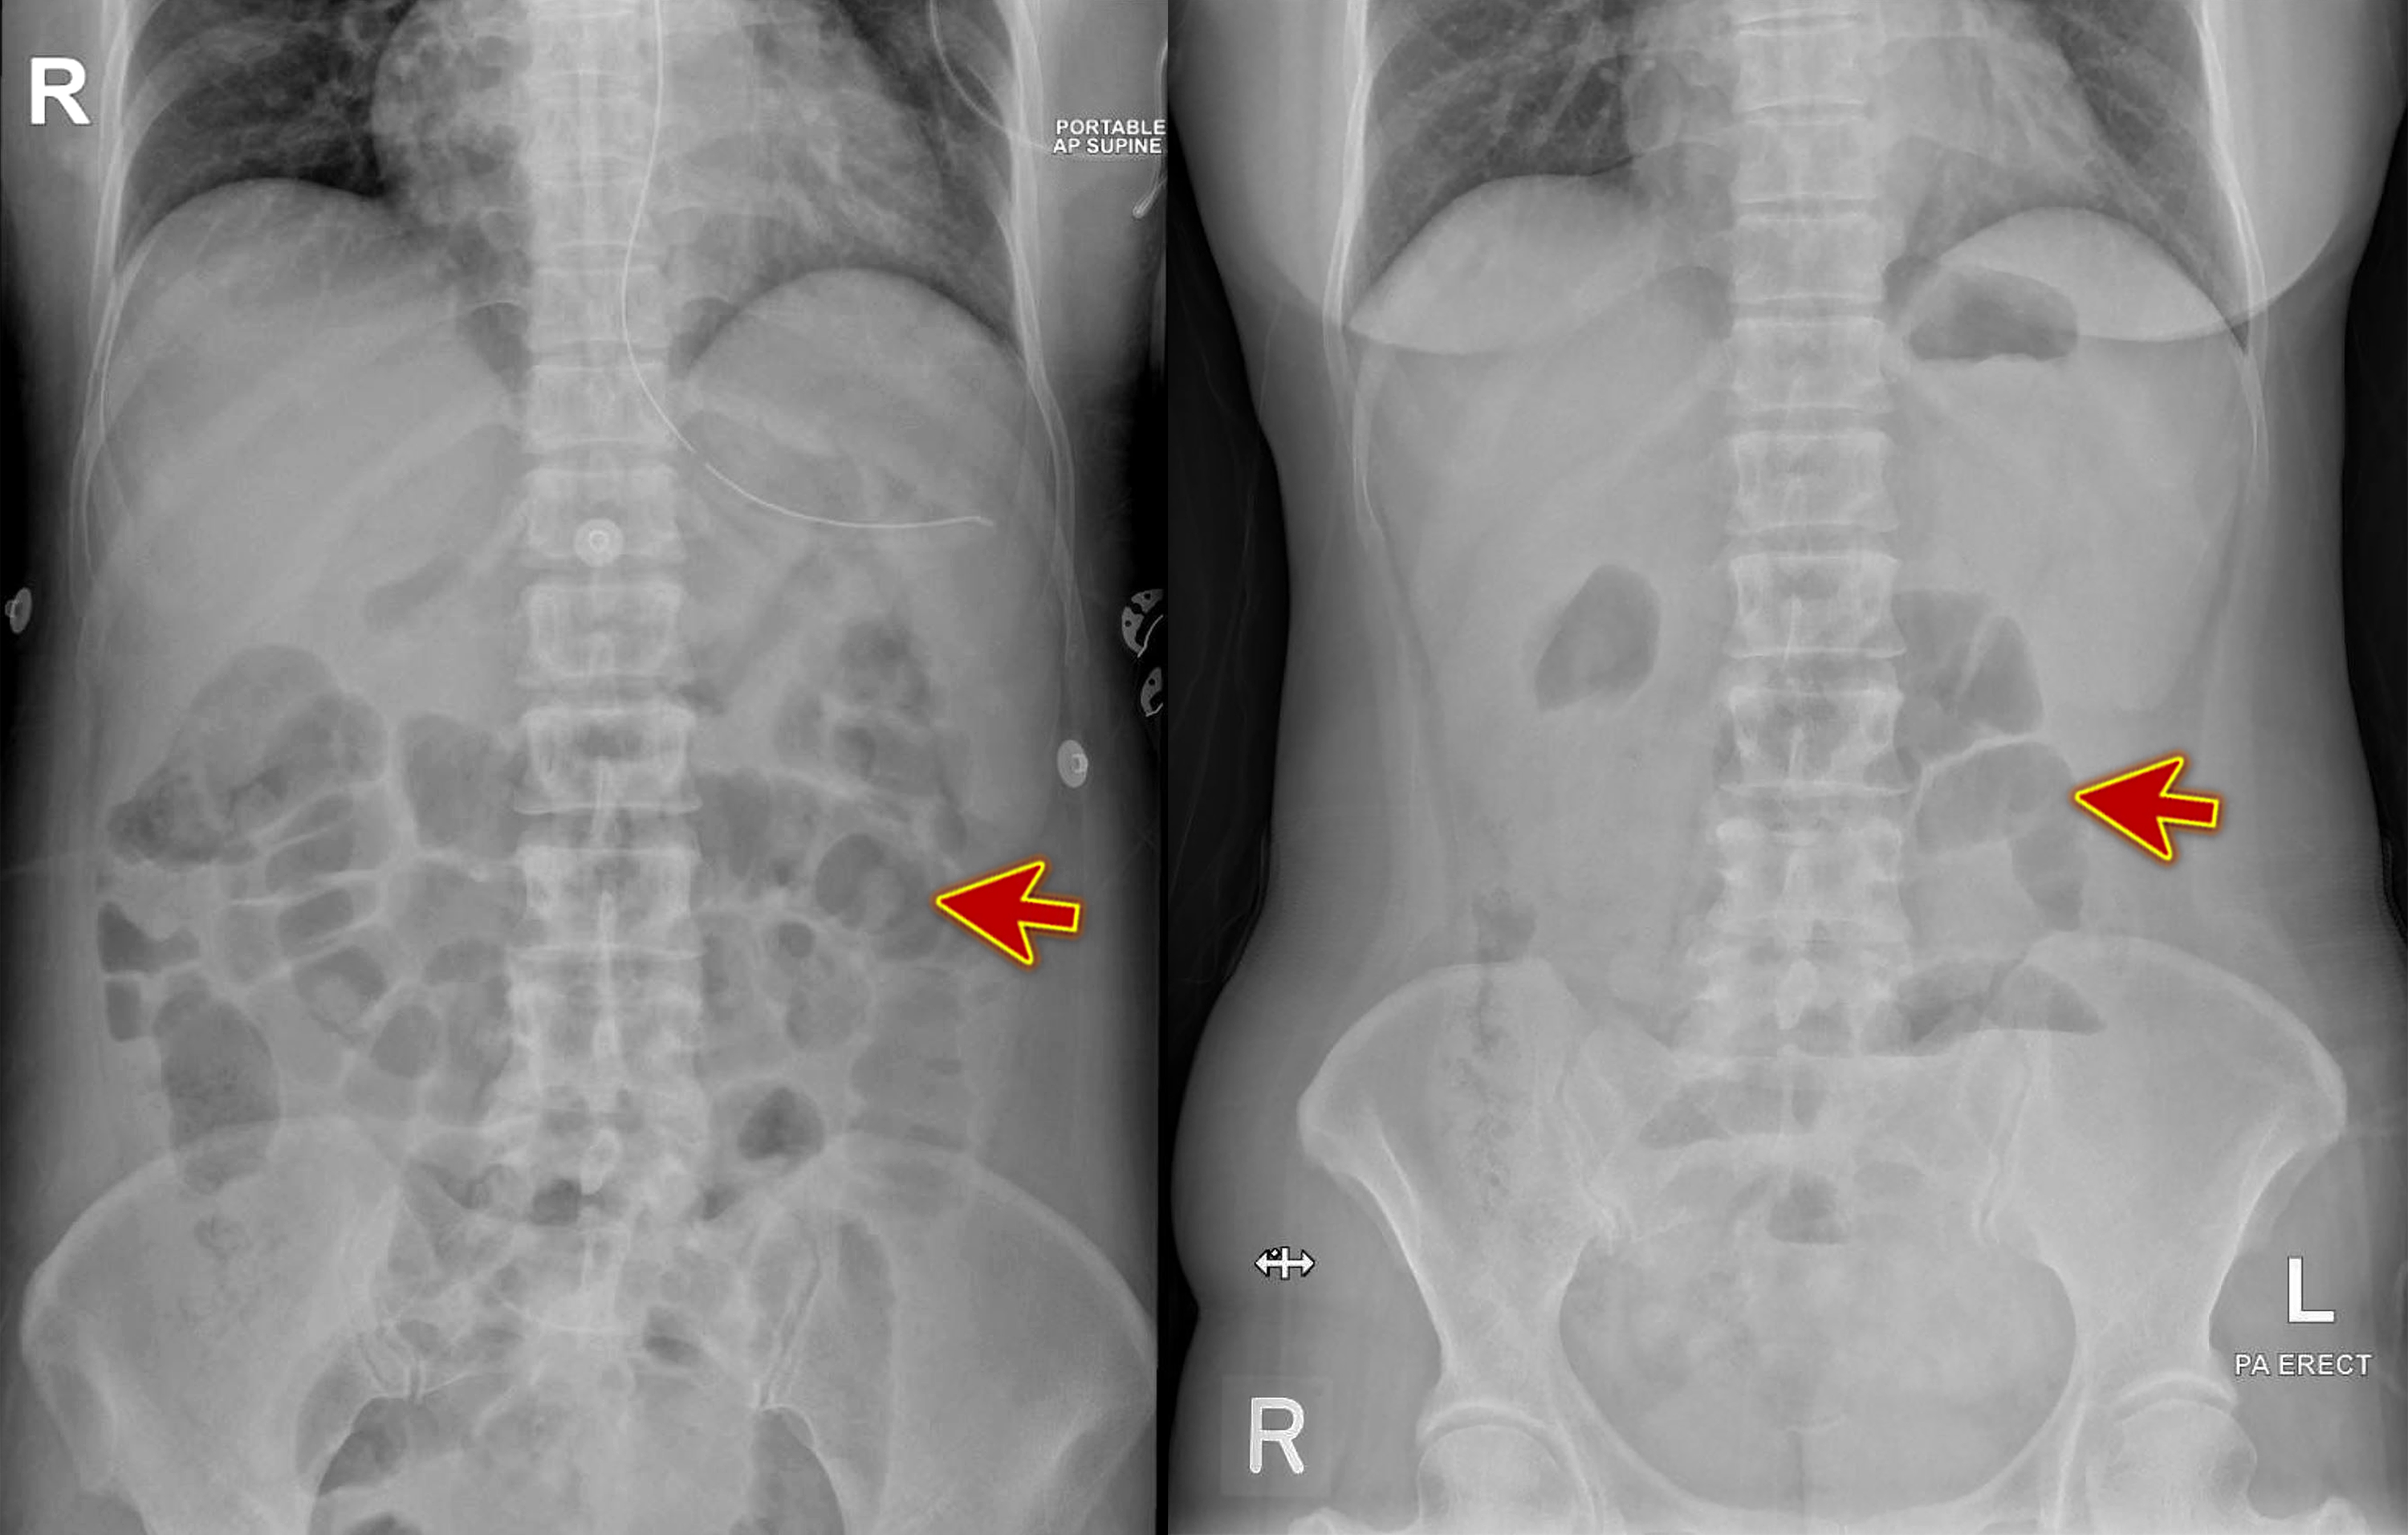

"Small intestine obstruction" Film Xray abdomen supine Stock Photo Alamy Cat Intestinal Blockage X Ray mechanical intestinal obstruction, lfb, lymphocytic plasmacytic enteritis, and intestinal lymphosarcoma are important differential. gastrointestinal obstruction is the blockage of the digestive tract. just like dogs, cats — especially young, curious cats — sometimes eat things that can get stuck in their. Cats who are experiencing an intestinal obstruction. The blockage can arise outside, within the. Knowing the. Cat Intestinal Blockage X Ray.